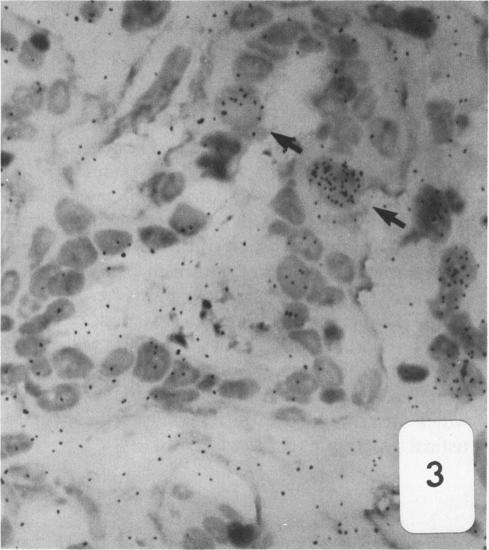

Dunning R3327-H rat prostate adenocarcinoma cells, when grown in syngeneic (Copenhagen) rats or nude mice, produce tumors with prominent hypercellular stroma. The authors have previously demonstrated the presence of anomalous steroid-sensitive cells in both the epithelium and stromal compartments of this model system. In order to better understand the histogenesis of these cells, the authors studied samples of the tumor which were radiolabeled overnight with tritiated dihydrotestosterone (3H-DHT). Frozen sections of the tissues were thaw-mounted onto autoradiographic emulsion-coated slides to permit silver grain identification in association with nuclei of androgen-sensitive cells. Surprisingly, numerous silver grains were found to be associated with nuclei of large cells within the stroma. Therefore, these cells were termed "epithelioid" pending confirmation of their origin. To further define these cells and their relationship to the surrounding matrix, autoradiograms have now been examined immunohistochemically with antibodies directed against the basement membrane glycoprotein, laminin, as well as antibodies specific for intermediate cytoskeletal filaments. Following identification of acinar basement membranes, epithelioid cells were identifiable both in the stroma and in the acinar epithelial cell layer. Histochemical staining with acid phosphatase, a marker for prostatic epithelium, was performed and shown to be present in acinar epithelial cells as well as in epithelioid cells. Additionally, fluorescence-activated cell sorting was employed to characterize the DNA content of cell types within the H tumor. Epithelioid cells were found to be in highest concentration in an aneuploid peak with a ploidy of approximately 6N. The autoradiographic, immunohistochemical, cytometric, and ultramicroscopic studies suggest that 1) epithelioid cells are epithelial derived stromal cells; 2) these epithelioid cells arise by pathologic division of aneuploid neoplastic precursor cells of approximately 3N ploidy, which are found within the prostatic epithelium; and 3) the resulting 6N cells degrade the basement membrane locally, invade the stroma, and populate it. Here, they can be distinguished from fibroblasts by their size, acid phosphatase activity, and hormone receptor content. Thus, the term "epithelioid" is inappropriate; and these cells should be regarded simply as large neoplastic epithelial (LNE) cells. The presence of this cell type suggests that this tumor subline represents a useful naturally occurring model for the study of the initial stages of neoplastic transformation.

邓宁R3327 - H大鼠前列腺腺癌细胞在同基因(哥本哈根)大鼠或裸鼠体内生长时,会产生具有显著细胞增多性基质的肿瘤。作者此前已证明在该模型系统的上皮和基质区室中均存在异常的类固醇敏感细胞。为了更好地理解这些细胞的组织发生,作者研究了用氚化双氢睾酮(3H - DHT)过夜进行放射性标记的肿瘤样本。将组织的冰冻切片解冻后贴在涂有放射自显影乳剂的载玻片上,以便确定与雄激素敏感细胞核相关的银颗粒。令人惊讶的是,发现大量银颗粒与基质内大细胞的核相关。因此,在确认其起源之前,这些细胞被称为“上皮样细胞”。为了进一步定义这些细胞及其与周围基质的关系,现在已用针对基底膜糖蛋白层粘连蛋白的抗体以及针对中间细胞骨架丝的特异性抗体对放射自显影片进行免疫组织化学检查。在确定腺泡基底膜后,在上皮样细胞的基质和腺泡上皮细胞层中均可识别出上皮样细胞。用酸性磷酸酶进行组织化学染色,酸性磷酸酶是前列腺上皮的标志物,结果显示其存在于腺泡上皮细胞以及上皮样细胞中。此外,采用荧光激活细胞分选技术来表征H肿瘤内细胞类型的DNA含量。发现上皮样细胞在非整倍体峰中浓度最高,其倍性约为6N。放射自显影、免疫组织化学、细胞计量学和超微结构研究表明:1)上皮样细胞是上皮来源的基质细胞;2)这些上皮样细胞由前列腺上皮内约3N倍性的非整倍体肿瘤前体细胞的病理性分裂产生;3)产生的6N细胞局部降解基底膜,侵入基质并在其中聚集。在这里,它们可以通过大小、酸性磷酸酶活性和激素受体含量与成纤维细胞区分开来。因此,“上皮样”这个术语并不恰当;这些细胞应简单地视为大肿瘤上皮(LNE)细胞。这种细胞类型的存在表明该肿瘤亚系是研究肿瘤转化初始阶段的一个有用的自然发生模型。